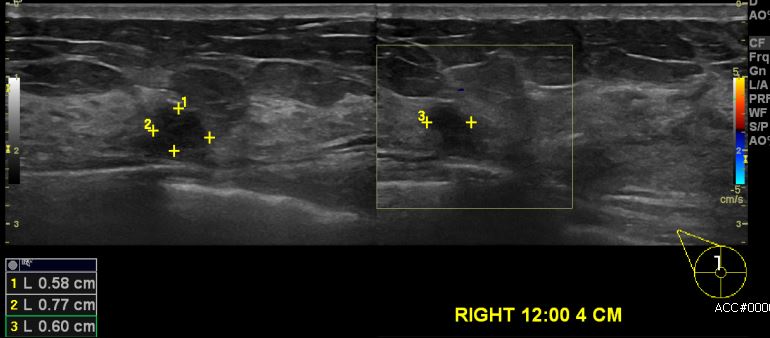

상기환자 2013년 건강검진상 이상 소견있어 추적관찰 권유 받으신 30대 여성분으로  2017년 6월 추적관찰 및 간헐적 유방 통증으로 본원 내원하시여 본원 초음파 시행 후 우측 12시 방향에서 4cm 떨어진 거리의 의심스러운 멍울 진공흡인유방절제술 시행하야 우측 소엽암 진단되었습니다.